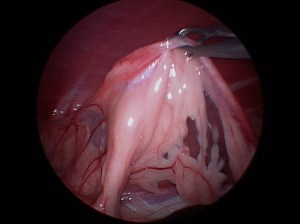

For the best possible outcome do not delay treatment! At this time, the gold standard approach is arthroscopic debridement (removal) of the fragmented cartilage and the surrounding diseased cartilage and subchondral bone. Curettage may allow the now vacant cartilage bed to fill in more quickly with what is called fibrocartilage. I likened the removal of the fragment to old wallpaper removal (very much oversimplified). Once the old wallpaper bubbles and tears, you need to remove all the damaged wallpaper in the periphery or else the wallpaper will continue to peel.

There are older techniques of opening the joint to get access to the cartilage flap, however the recovery time on this type of procedure is significantly longer than with arthroscopy. Also, potential complications are increased with an “open” technique than with arthroscopic techniques. Arthroscopy is a minimally invasive tool that allows us to both diagnose and treat this condition. Generally speaking the patient can walk on the surgery leg (even if both legs have surgery at the same time!) following an arthroscopic procedure. Generally 2-3 small ports are placed over the shoulder (2-4mm in length) and this allows us access to the joint and work within the joint.